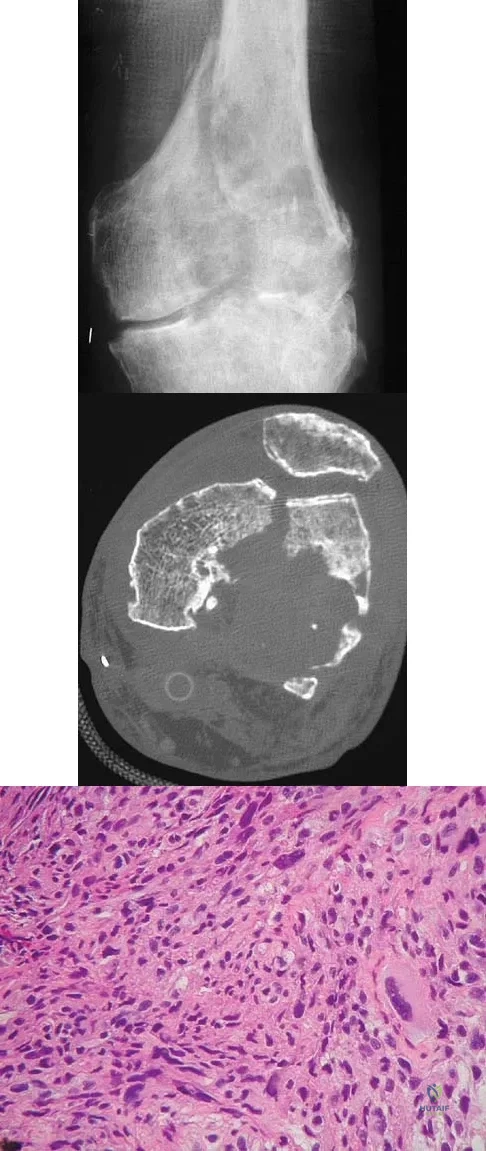

A 50-year-old man with metastatic renal cell carcinoma has right hip pain. A radiograph and CT scan are shown in Figures 48a and 48b. The first step in management should consist of

Explanation

A 23-year-old woman has had vague left knee pain for the past 6 months. A radiograph and CT scan are shown in Figures 50a and 50b. What is the most likely diagnosis?

Explanation